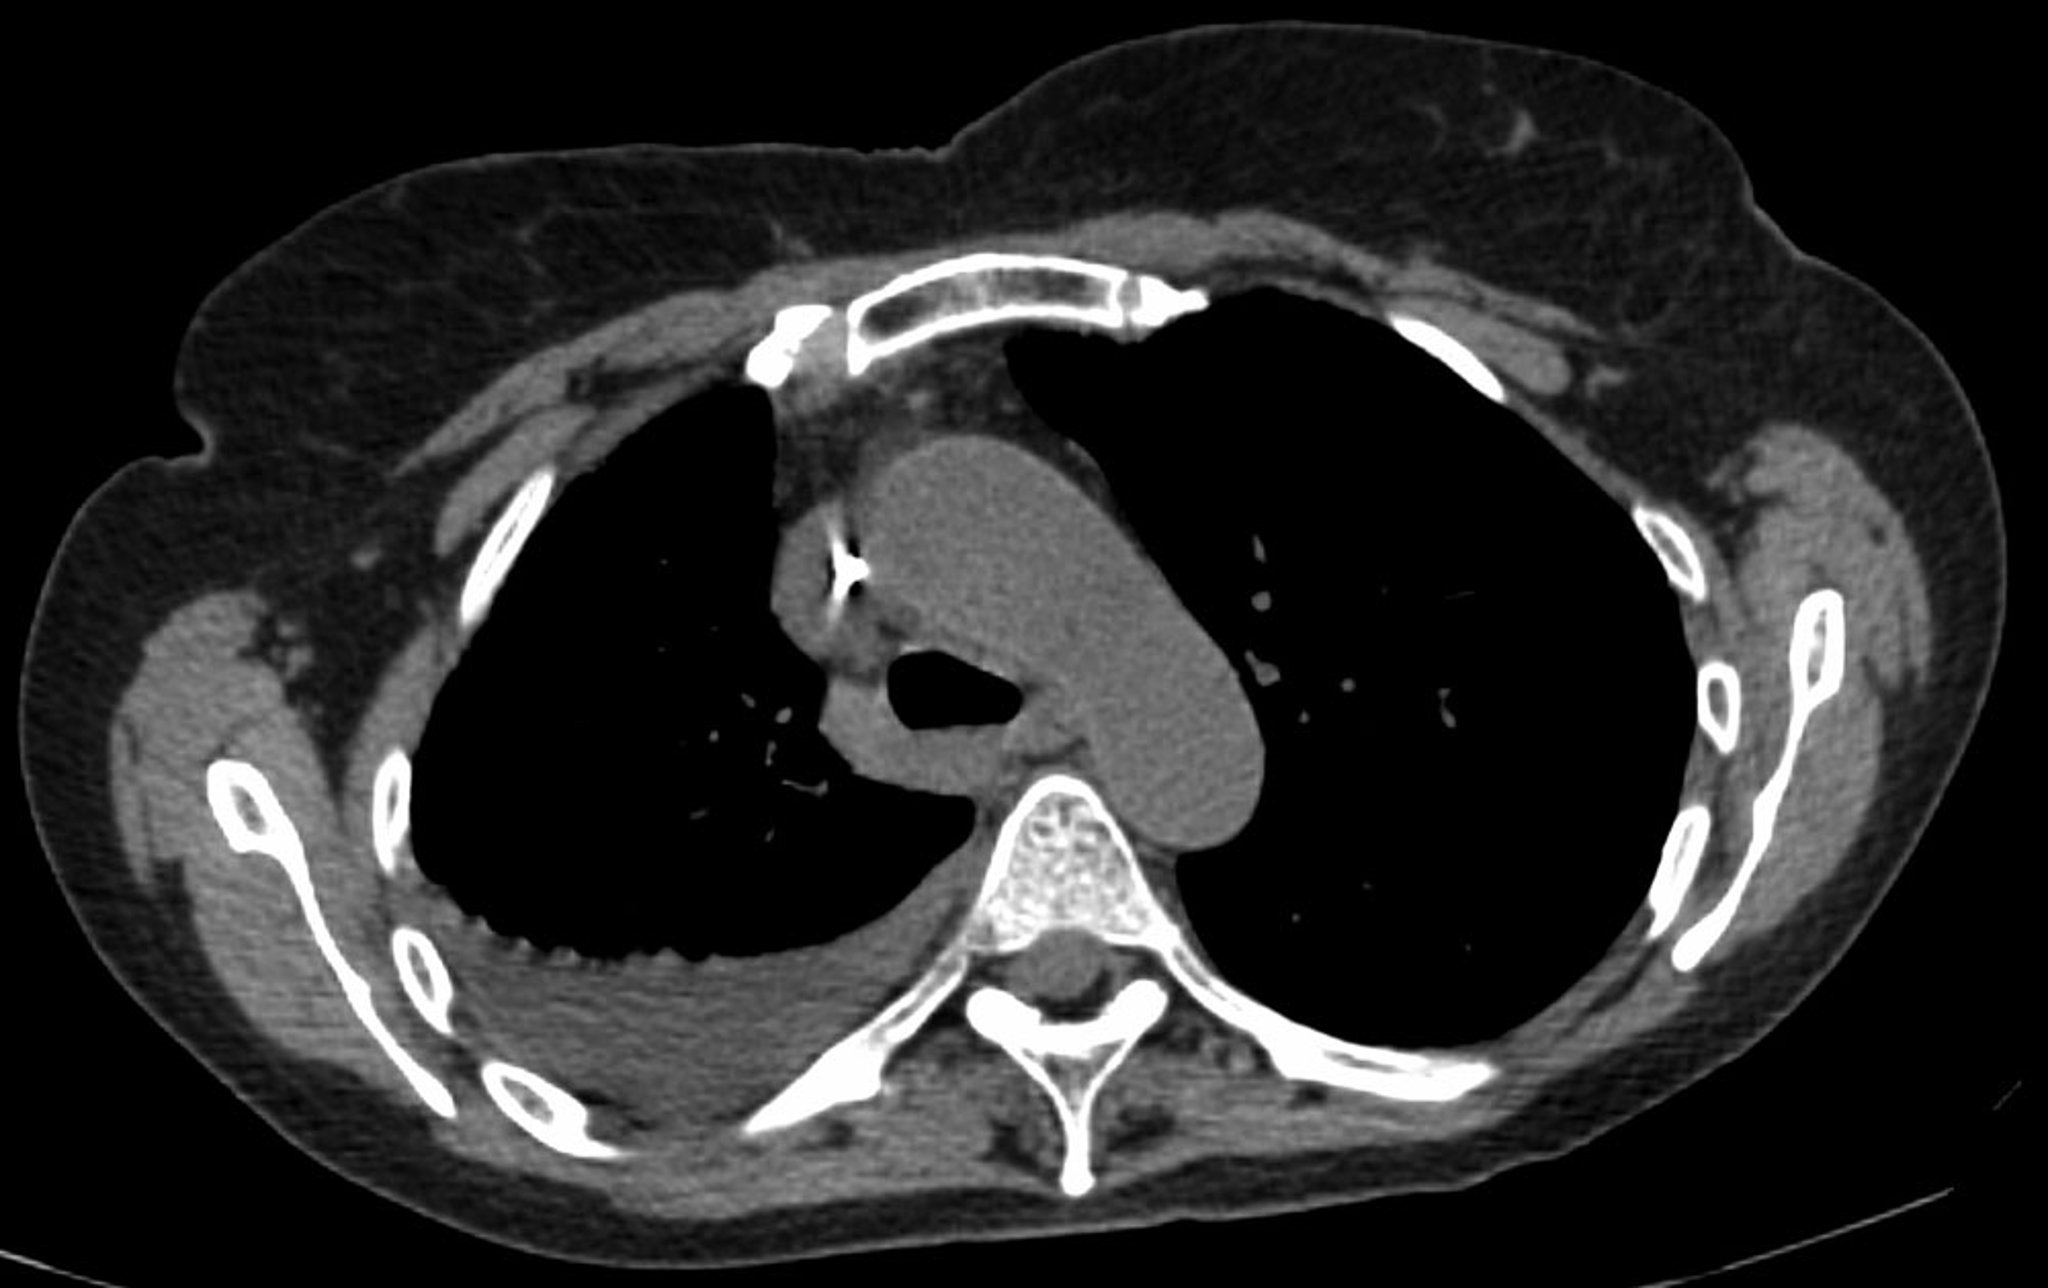

右侧胸腔积液(CT扫描)

这张胸部轴位非增强CT图像显示乳腺癌女性患者右侧中小量胸腔积液。(纵隔CT扫描窗口)